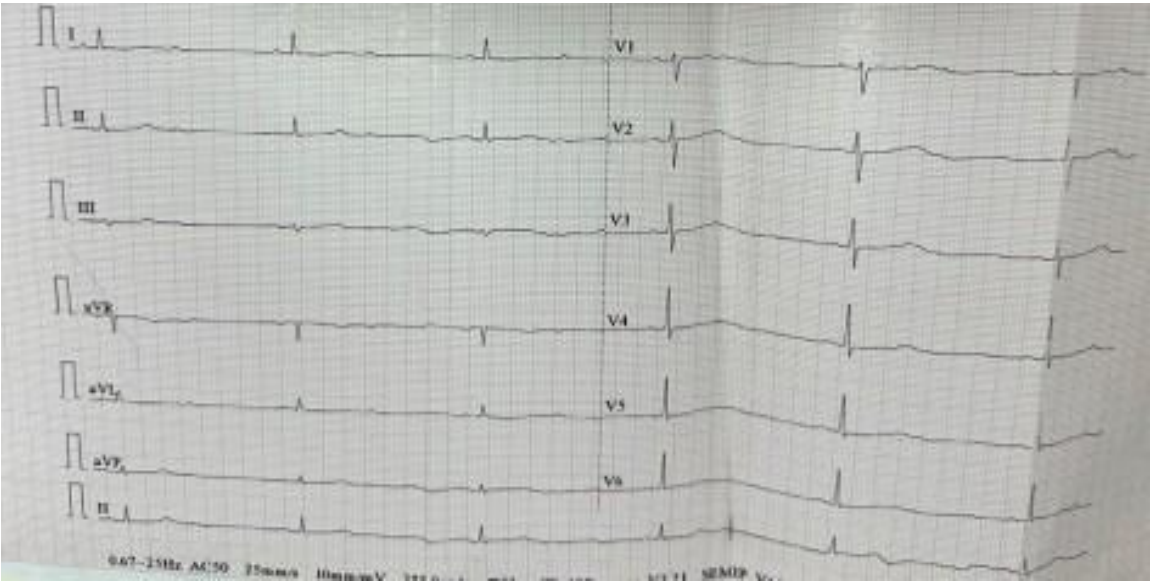

Clinical examination revealed a blood pressure of 150/90 mmHg and bradycardia with a heart rate of 33 beats per minute, along with the presence of a retrosternal goiter on neck examination. The remainder of the physical examination was unremarkable. The electrocardiogram (ECG) showed a high-degree 2:1 AVB with a junctional escape rhythm at 33 beats per minute.

Figure 1. ECG showing high-degree 2:1 atrioventricular block with an escape rhythm at 33 bpm